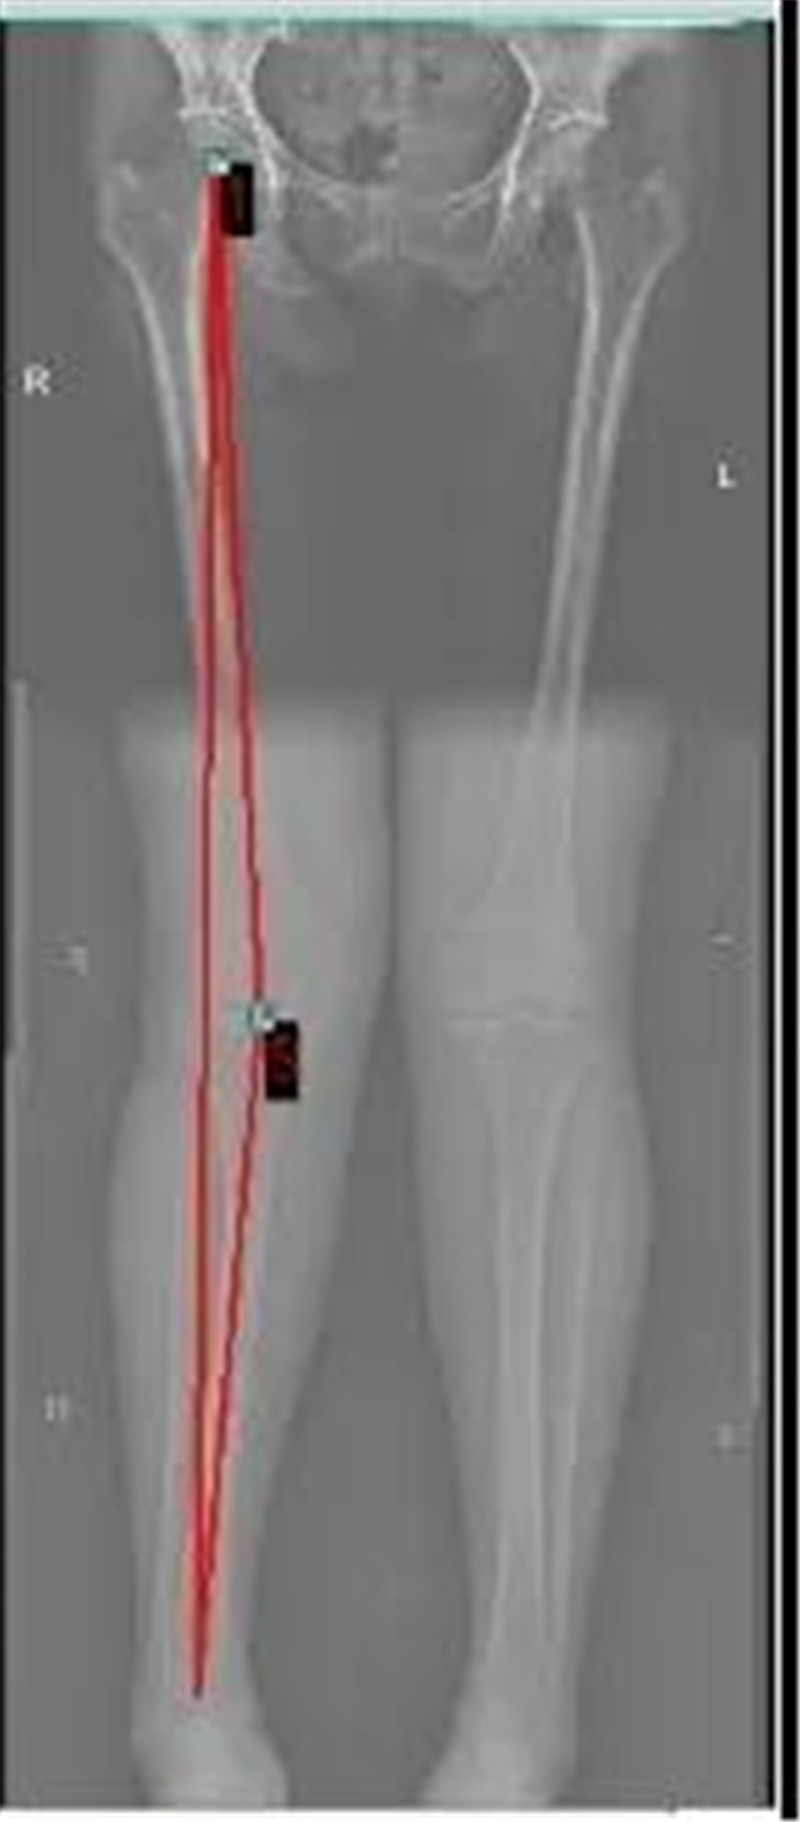

“X”型腿(外八字)和 “O”型腿(内八字)

X型腿矫正对比